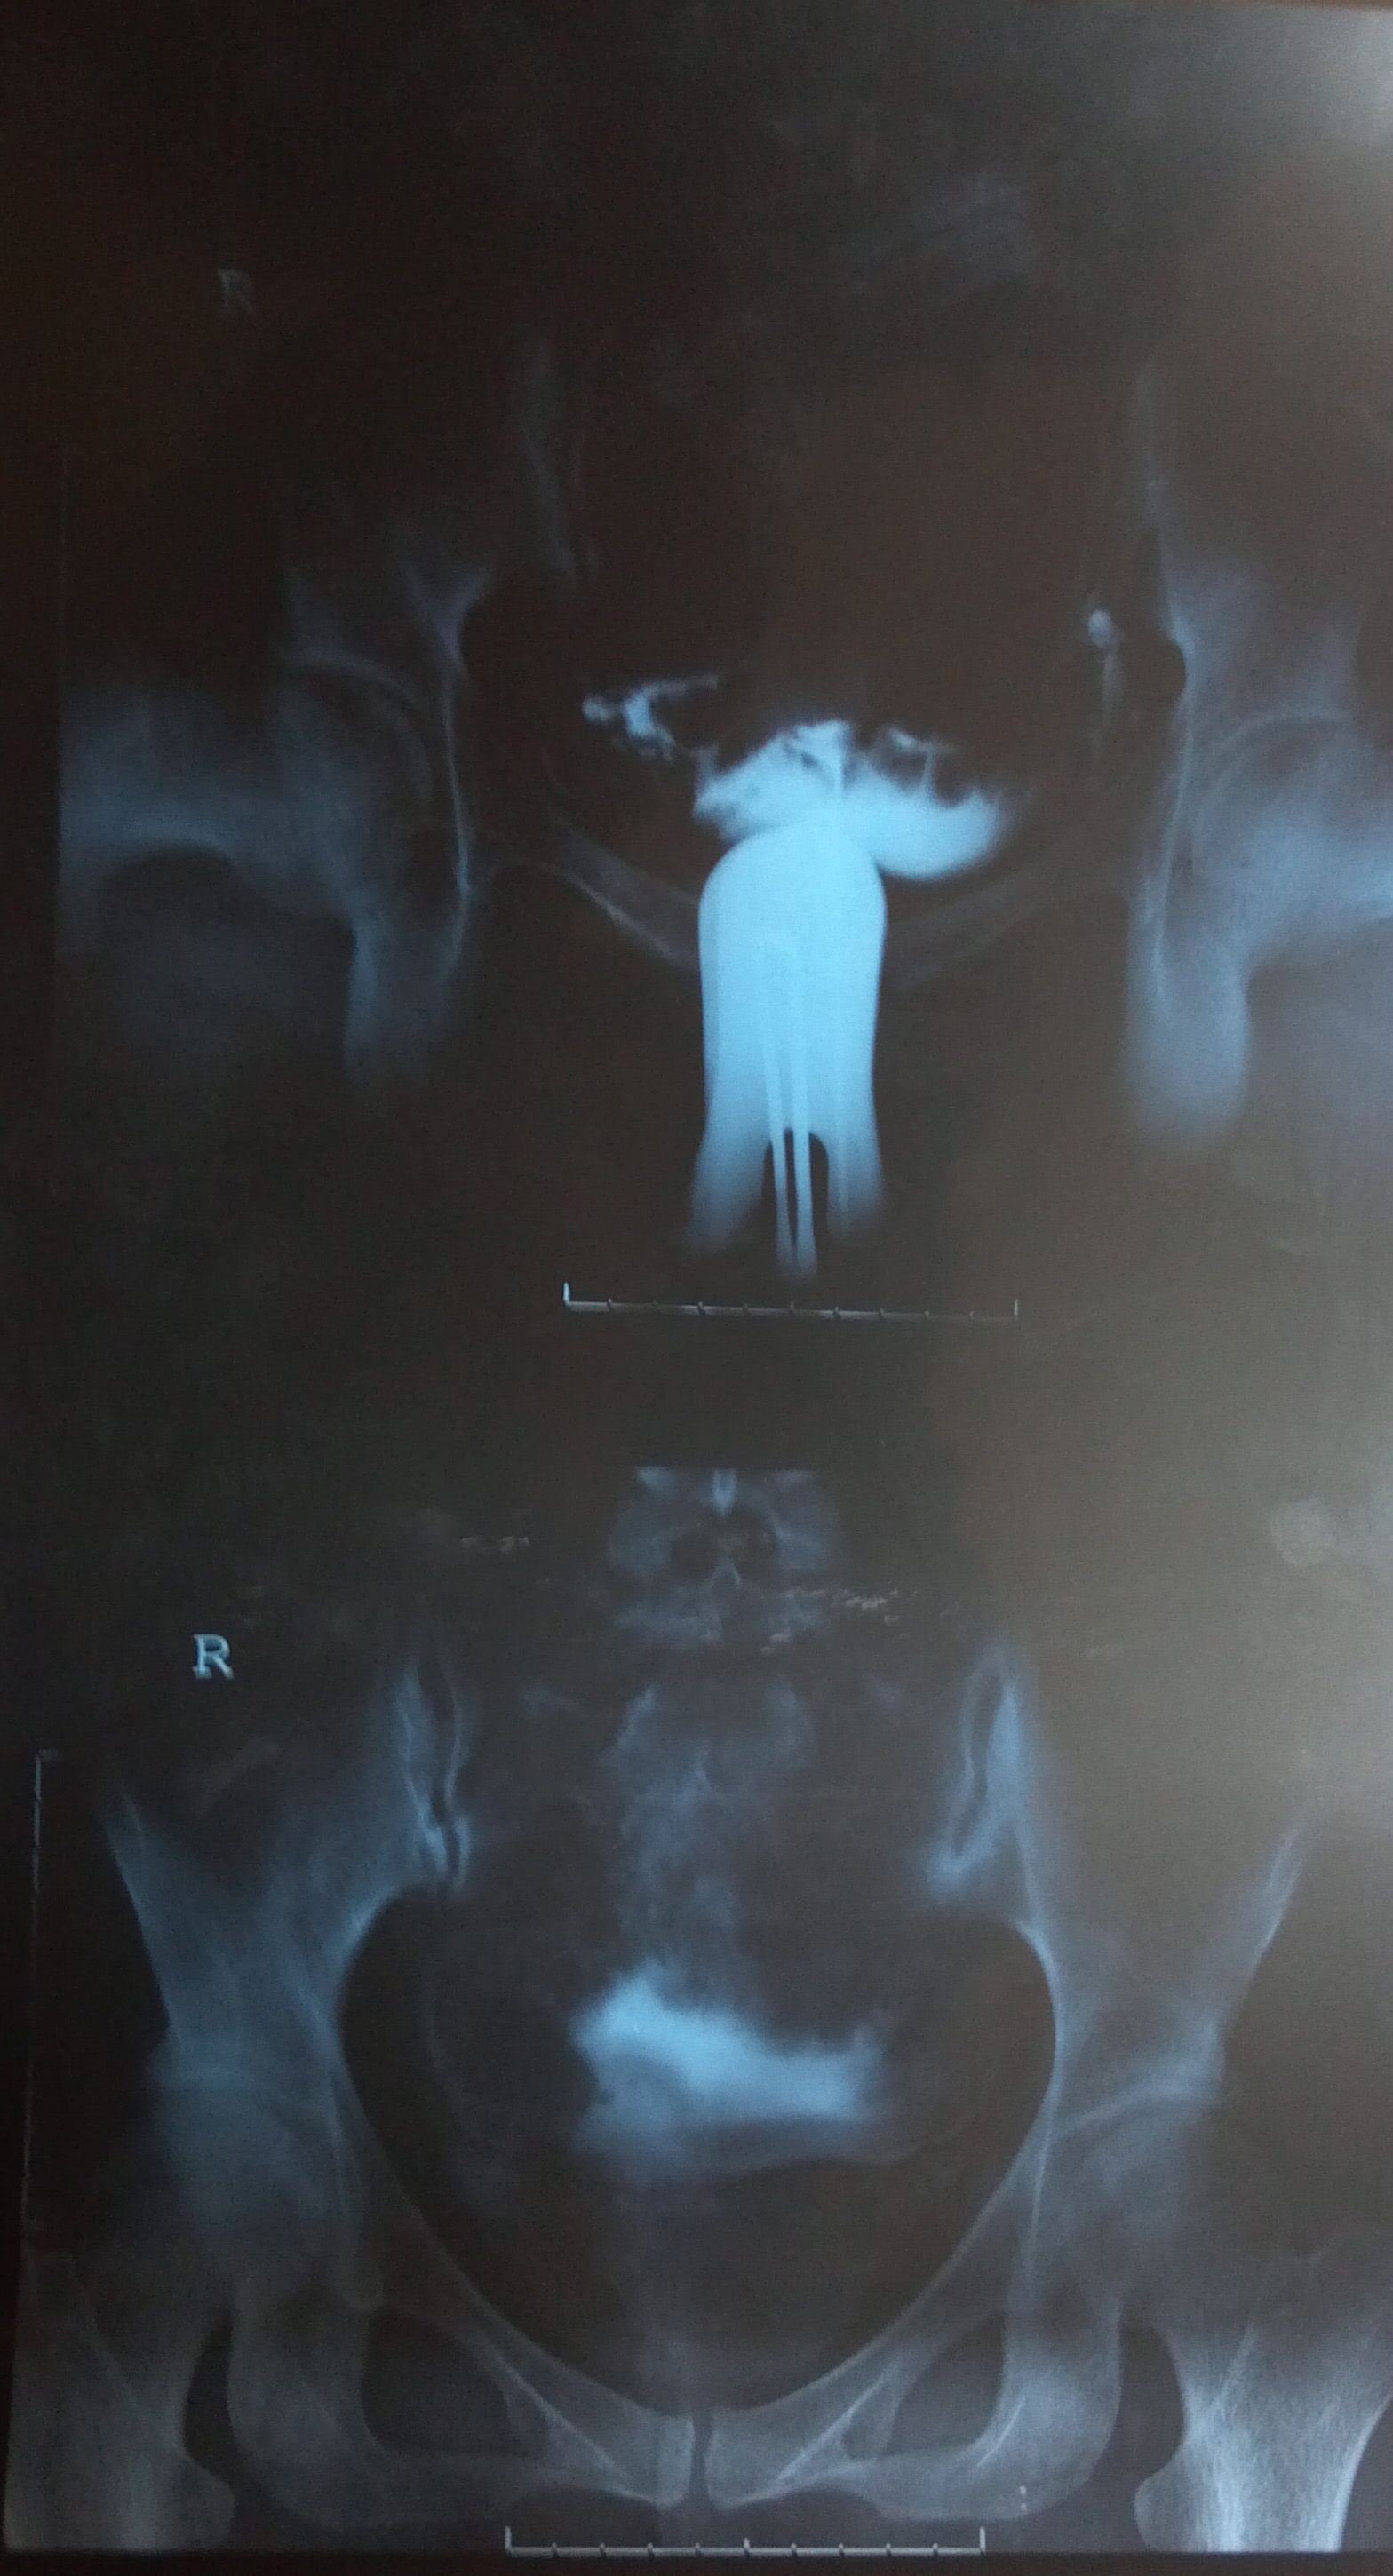

我去年8月做了造影 2年没有怀上小孩 以前做过人流,我想知道我的造影会影响怀孕吗?输卵管有粘连和积水? 点击展开 匿名用户 2013-03-05 13:53 为您推荐: 其他回答 你好, 你现在的情况需要进行保守治疗,由于你的是双侧的输卵管炎,用逐水舒管汤就可以了 匿名用户 2013-03-05 16:41 相关问题 我是去年9月做的人流,今年想怀孕,但是一直没有怀上,我需要做输卵管造影吗 怀孕九个多月了,现在查出小孩脑积水38,30小孩能要吗 09年开刀生过一个小孩 2011年怀孕 一次 当时不能要小孩 医生建议吃药人流没有感觉